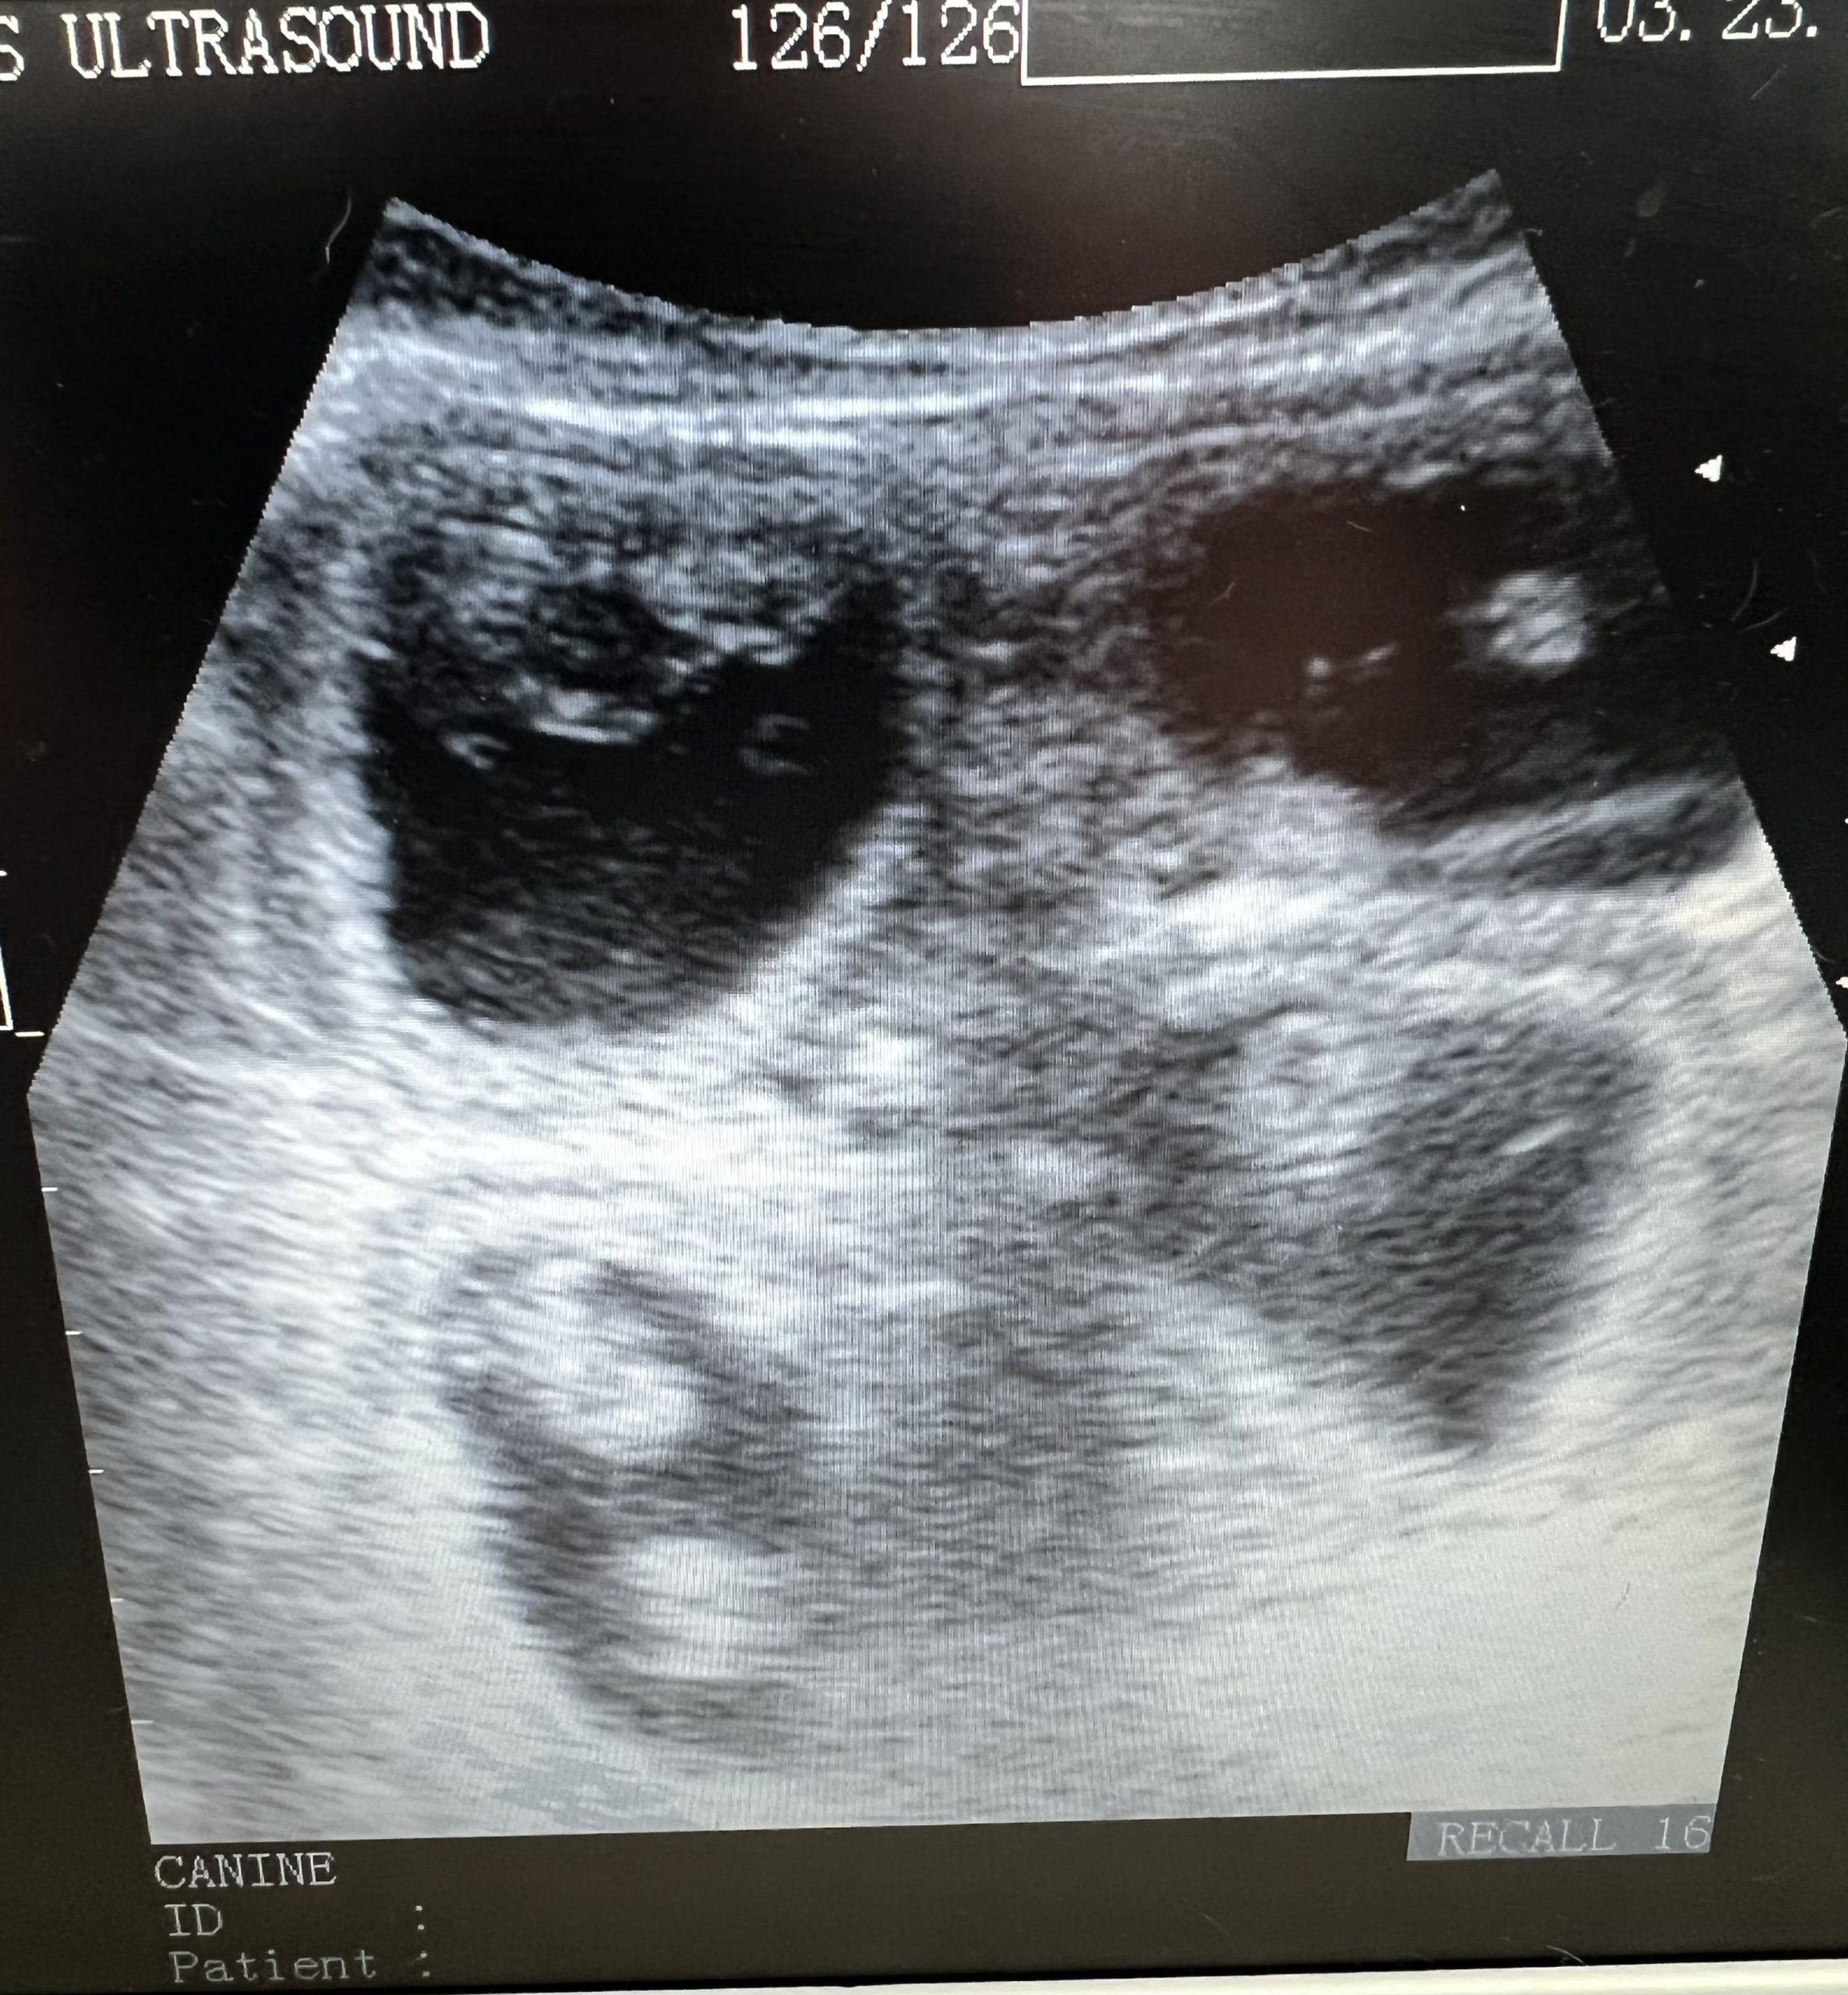

Natal Scan for Bella the Lhaso Apso

We conducted a scan for Bella to confirm pregnancy and was able to positively confirm between 4 and 6 pregnancies, with well developed, active pups. Estimated delivery date of the